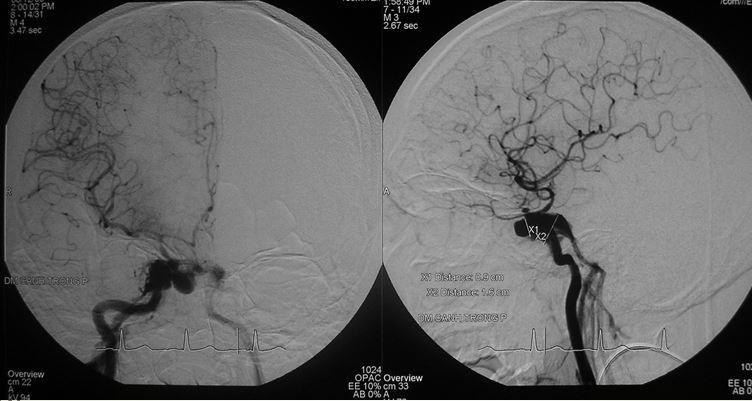

Một trường hợp khác được BS Trần Chí Cường can thiệp năm 2007 là một bé gái 14 tuổi, thường xuyên bị đau đầu, ngất xỉu khi gắng sức, động kinh toàn thể trong thời gian dài không được chẩn đoán và điều trị dị dạng thông động tĩnh mạch não bẩm sinh.

Dị dạng thông động tĩnh mạch não bẩm sinh AVM-AVF

Trường hợp này khiến BS Cường phải suy nghĩ nhiều đêm, cuối cùng tìm ra phương pháp double catheter, giống như “đắp đập” từ từ để giảm dòng chảy. Kỹ thuật này sau đó đã được áp dụng điều trị thành công cho nhiều bệnh nhân khác, BS Cường cũng báo cáo với thế giới và được ghi nhận là một kỹ thuật can thiệp nội mạch thuộc bản quyền của bác sĩ Việt Nam, được các nước học hỏi.

Hình ảnh DSA thực hiện kỹ thuật double catheter